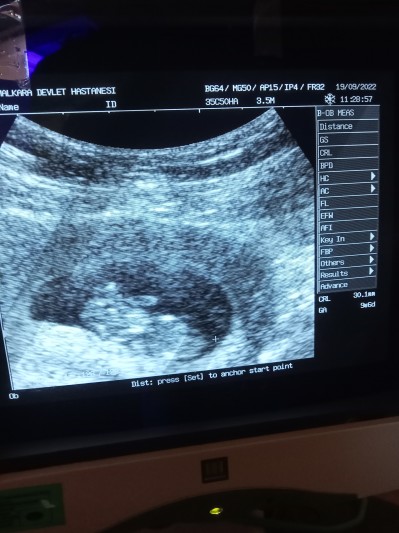

10+ cinsiyet tahmini alabilirmiyim

Kizlar tahmin nedir belli olurmu acaba bebisimin

10+

bu hafta da biraz zor cinsiyet öğrenmek böyle resimle anlaşılmaz ki canım 2 hafta sonra doktorun tahmin de bulunur zaten